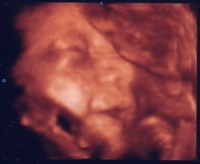

Vanoval minden rendben, dobog a kis szivecskeje, szep a fejecskeje, lattuk a kis veseit, mindene ok szerencsere, eppen szundikalt az uh alatt